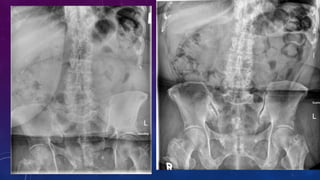

• Multiple pelvic phleboliths.

• Small well-defined round osseous lesions in the left

side of the abdomen, adjacent to midline represent

calcified lymph node in the para-aortic and left

common iliac groups, also visualized on the

corresponding CT.